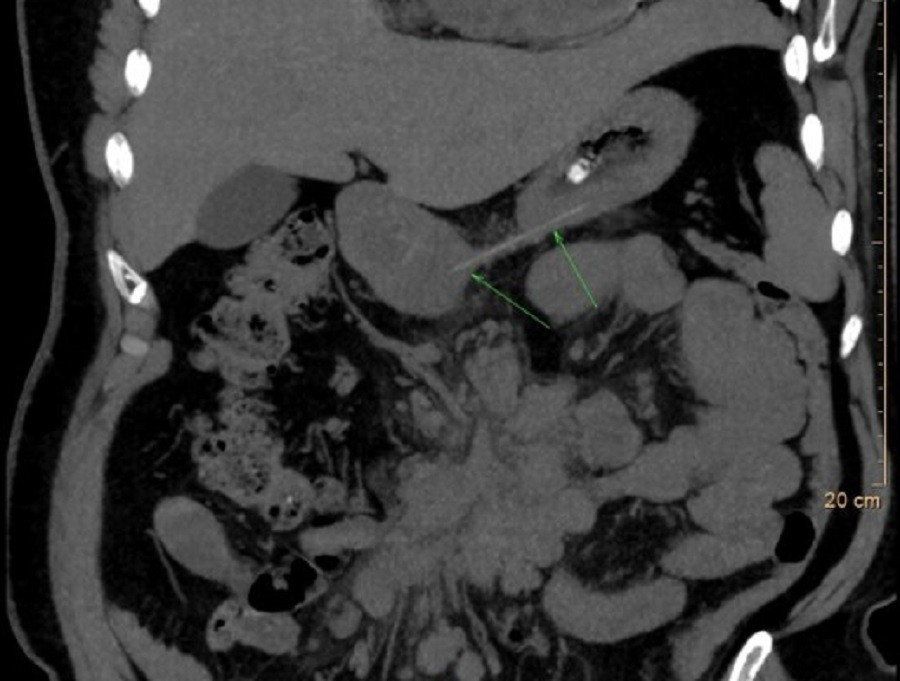

Khi đến bệnh viện, bệnh nhân đã có dấu hiệu khó thở nghiêm trọng. Nội soi thanh quản cho thấy sụn thanh và sụn phễu phù nề nặng, che lấp gần như toàn bộ đường thở. CT xác định phù nề dày ở thanh thiệt, sụn phễu và đáy lưỡi, tạo nguy cơ tắc nghẽn đường thở cao.

Nhờ can thiệp nội soi lấy dị vật, kết hợp kháng sinh, kháng viêm, phun khí dung và giảm đau, tình trạng phù nề giảm dần, các triệu chứng hô hấp cải thiện rõ rệt.